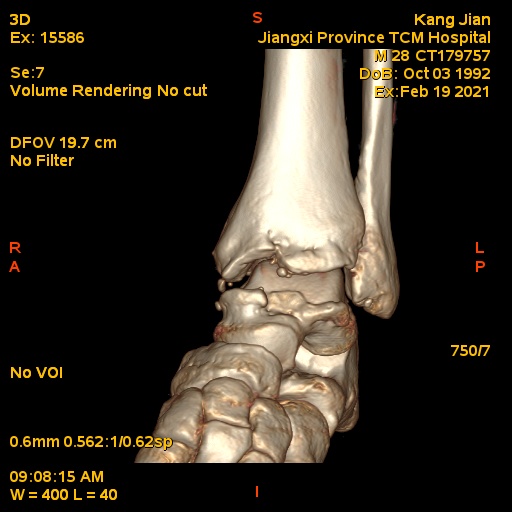

患者,男,28岁,有踝关节扭伤史,患者10天前扭伤致左踝疼痛伴活动受限。查体:左踝关节轻度肿胀,关节缘广泛性压痛,未扪及骨擦音及骨擦感,局部皮肤无瘀青、无皮损,外翻应力试验阳性,抽屉试验阳性,肢端感觉及血运正常。